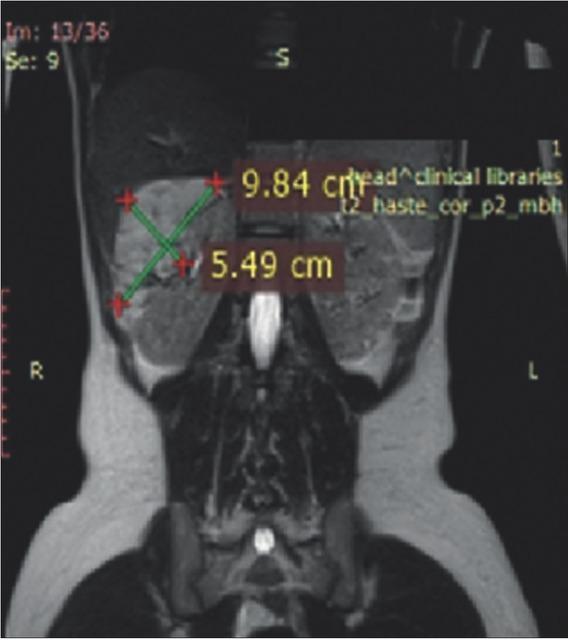

Figure 3

Magnetic resonance imaging of the urinary tract at 12 months after everolimus initiation.

Magnetic resonance imaging of the urinary tract and brain were performed before initiation of everolimus treatment (Figures 1 and 2). After 12 months of treatment, reduction of the renal tumors and SEGA were registered (Figures 3 and 4). At 36 months, ~24.0% reduction in the longest diameter of the largest AML in right kidney was achieved. Reduction of SEGA was also observed (Figures 5 and 6). All biochemical parameters remained stable during the follow-up period. Normal renal function without a new onset of proteinuria was observed (Table 2).

Magnetic resonance imaging of the urinary tract at 36 months after everolimus treatment initiation.

Figure 6

After 3 years of treatment, our patient reached approximately 24.0% reduction in the longest diameter of AML. No evidence of new AMLs or episodes of bleeding were observed.